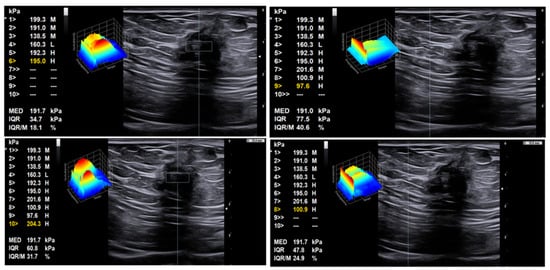

7. Discussion